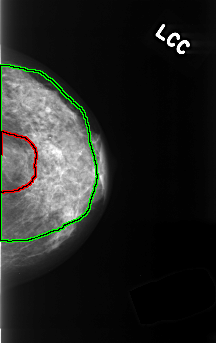

FILE: C_0366_1.LEFT_CC.OVERLAY

TOTAL_ABNORMALITIES 2

ABNORMALITY 1

LESION_TYPE MASS SHAPE ROUND MARGINS ILL_DEFINED

ASSESSMENT 4

SUBTLETY 4

PATHOLOGY BENIGN

TOTAL_OUTLINES 1

BOUNDARY

ABNORMALITY 2

LESION_TYPE CALCIFICATION TYPE PLEOMORPHIC DISTRIBUTION DIFFUSELY_SCATTERED

ASSESSMENT 3

SUBTLETY 3